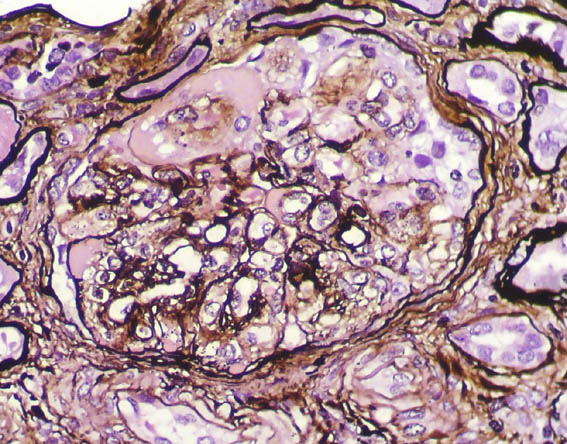

Methenamine-silver stain, X400.

Figure 6. Methenamine-silver stain, X400.